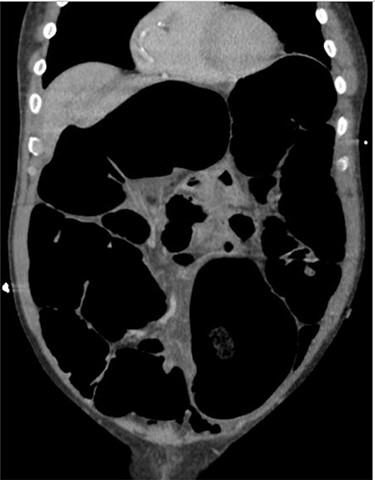

Blood tests on admission were unremarkable. Each admission, the patient’s plain abdominal films showed dilated large bowel loops consistent with sigmoid volvulus (Fig. 1). A subsequent computed tomography (CT) of the abdomen and pelvis with intravenous contrast revealed dilated large bowel and was reported as sigmoid volvulus with no evidence of perforation (Fig. 2). Caecal volvulus was not appreciated on this scan.

Case one: coronal slice of a CT scan of the abdomen and pelvis with intravenous contrast showing dilated large bowel.